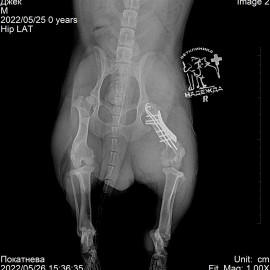

Наш пациент собака породы такса. Обратились в клинику с жалобами на отёк на правой задней лапе и потерю опороспособности. Были проведены исследования. Поставлен диагноз: перелом правого бедра. Проведена операция: остеосинтез правого бедра.

Снимок 1 до операции.